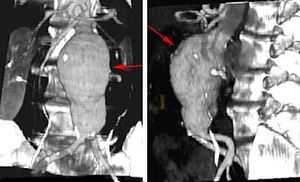

- في أجزاء الشريان الأبهر. الشريان الأبهر يحمل الدم من القلب إلى أجزاء أخرى من الجسم. تمدد الأوعية الدموية الأبهري يمكن أنْ يحدث في المنطقة أسفل المعدة (تمدد أوعية دموية بطني) أو في الصدر (تمدد أوعية دموية صدري). تمدد الأوعية الدموية البطني الأبهري يقع عادة تحت الكلى.

تعتمد المعالجة على حجم وموقع التمدد وصحة المصاب العامة. تمدد الأوعية الدموية في قسم الصدر الأعلى (الشريان الأبهر الصاعد) يخضع للجراحة فورا. تمدد الأوعية الدموية في القسم الصدري الأوطأ والمنطقة أسفل المعدة (أجزاء صدرية وبطنية من الشريان الأبهر) قد لا يشكل خطر يهدد حياة المصاب. التمدد في هذه المواقع يتم مراقبته بإنتظام. إذا وصل إلى قطر 5 سنتيمترات (تقريبا بوصتان)، أو واصل النمو، أو بدأ بالتسبّب بأعراض مزعجة، فيمكن اللجوء أيضا للجراحة لإيقاف تمدد الأوعية الدموية قبل إنفجارها.

الإجراء يتضمن إستعمال قسطرة لإدخال أداة تسمى وصلة حلقة فاتحة Stent Graft. الحلقة الفاتحة توضع داخل الشريان في موقع التمدد. يجرى الدم خلال الحلقة الفاتحة، مما يؤدي إلى خفض الضغط على جدار الشريان الضعيف. هذا الإنخفاض في الضغط يمكنه أن يمنع التمدد من تفجير الشريان.